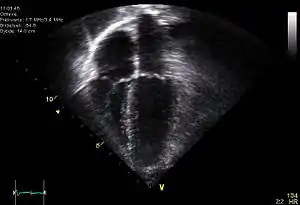

Ехокардіографія

Ехокардіографі́я — неінвазивний метод дослідження серця та магістральних судин за допомогою ультразвуку.[1] Дозволяє візуалізувати анатомічні особливості та оцінити функцію серця та магістральних судин. У медицині застосовують ультразвук (УЗ) частотою 1-1,5 МГц.